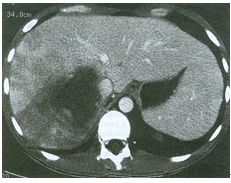

18. 50歲的女性因上腹痛接受上消化道內視鏡檢查並做了病理切片(如圖A及B所示),全身電腦斷層和骨髓檢查發現除了胃以外並無任何異常,請問最適合的初步治療為何?

(A) subtotal gastrectomy with BII anastomosis (B) chemotherapy with cyclophosphamide, doxorubicin, oncovin and prednisolone (C) triple therapy with proton pump inhibitor, clarithromycin & amoxicillin (D) target therapy with sunitinib (E) radiotherapy